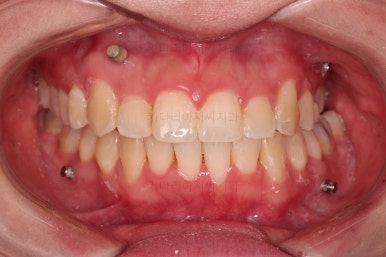

초진 시 입안의 모습입니다.

전반적으로 치열이 삐뚤고요.

위아래 중앙선이 약간 틀어져 있는데 많이 심한 편은 아니고요. 윗니가 배열된 U자 형태를 보면 아랫니보다 좁은 형태로 "악궁이 좁은" 상황이었습니다.